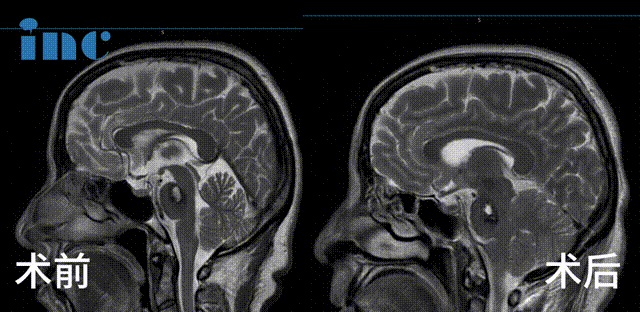

▼术前及术后1天影像对比

2023年9月28日,巴教授于苏州大学附属独墅湖医院为金女士顺利手术,巴教授成功为金女士取出了这颗脑干位置的不定时炸弹,无任何新发神经功能损伤,同时巴教授也成功进行了面神经解压术,解决了金女士面肌痉挛的问题。

术后1天ICU查房,金女士感觉状态良好,四肢活动正常。术后2天查房,金女士已经可以坐起,面部没有麻木。